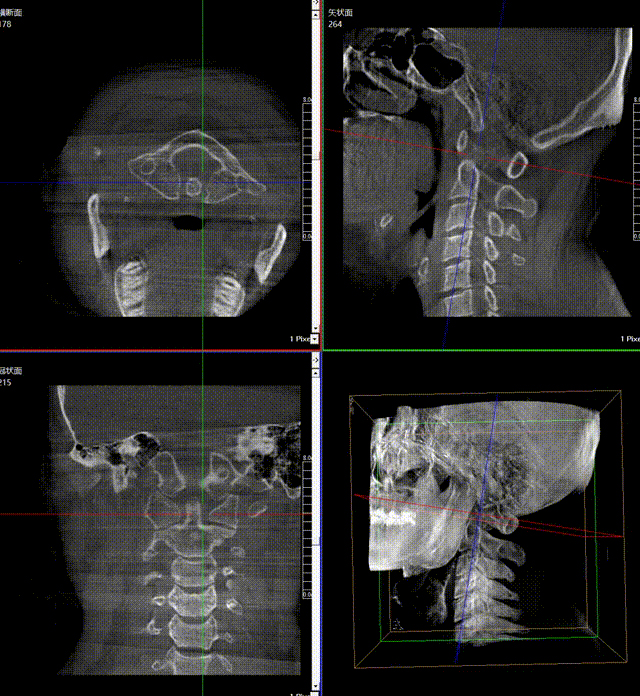

通常上頸椎的手術(shù)是非常復(fù)雜的,因?yàn)獒t(yī)生要把釘子打在上頸椎這樣一個(gè)很狹小的通道里面,周圍都是重要的神經(jīng)血管,一旦損傷到頸椎,就有可能造成病人的死亡。隨著醫(yī)學(xué)影像技術(shù)的不斷發(fā)展,在三維影像的引導(dǎo)下,整個(gè)打進(jìn)去的通路能夠完全的展現(xiàn)在我們的眼睛里,讓這種復(fù)雜的手術(shù)變得簡(jiǎn)單了,更多的醫(yī)生就可以去開展這樣的手術(shù)了,也會(huì)有越來(lái)越多的病人從中獲益。